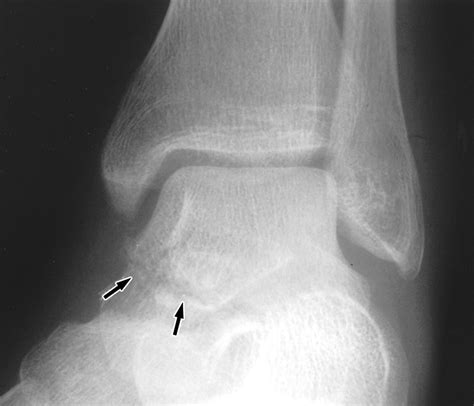

When you experience a sudden, sharp pain in a joint followed by swelling, you might be dealing with an avulsion fracture. This injury occurs when a small chunk of bone attached to a tendon or ligament gets pulled away from the main part of the bone. Unlike a typical break, this injury involves the soft tissue putting enough tension on the bone to cause a fracture at the attachment site. One of the most common treatments recommended by orthopedists is a cast for avulsion fracture, which serves to immobilize the affected area, allowing the bone to knit back together without the stress of daily movement.

Avulsion fractures are frequently seen in athletes, particularly those involved in sports requiring sudden changes in direction or explosive power. Common sites for these injuries include the ankle, hip, finger, and base of the fifth metatarsal in the foot. When a muscle contracts forcefully, it can pull on its tendon, and if the force is excessive, the bone simply gives way. Because the movement of tendons is constant, the primary goal of medical intervention is complete restriction. Using a cast for avulsion fracture ensures that the tendon does not pull the bone fragment further out of alignment while the healing process begins.

Ankle (Malleolar) Fiberglass/Plaster Cast Restrict joint rotation and inversion